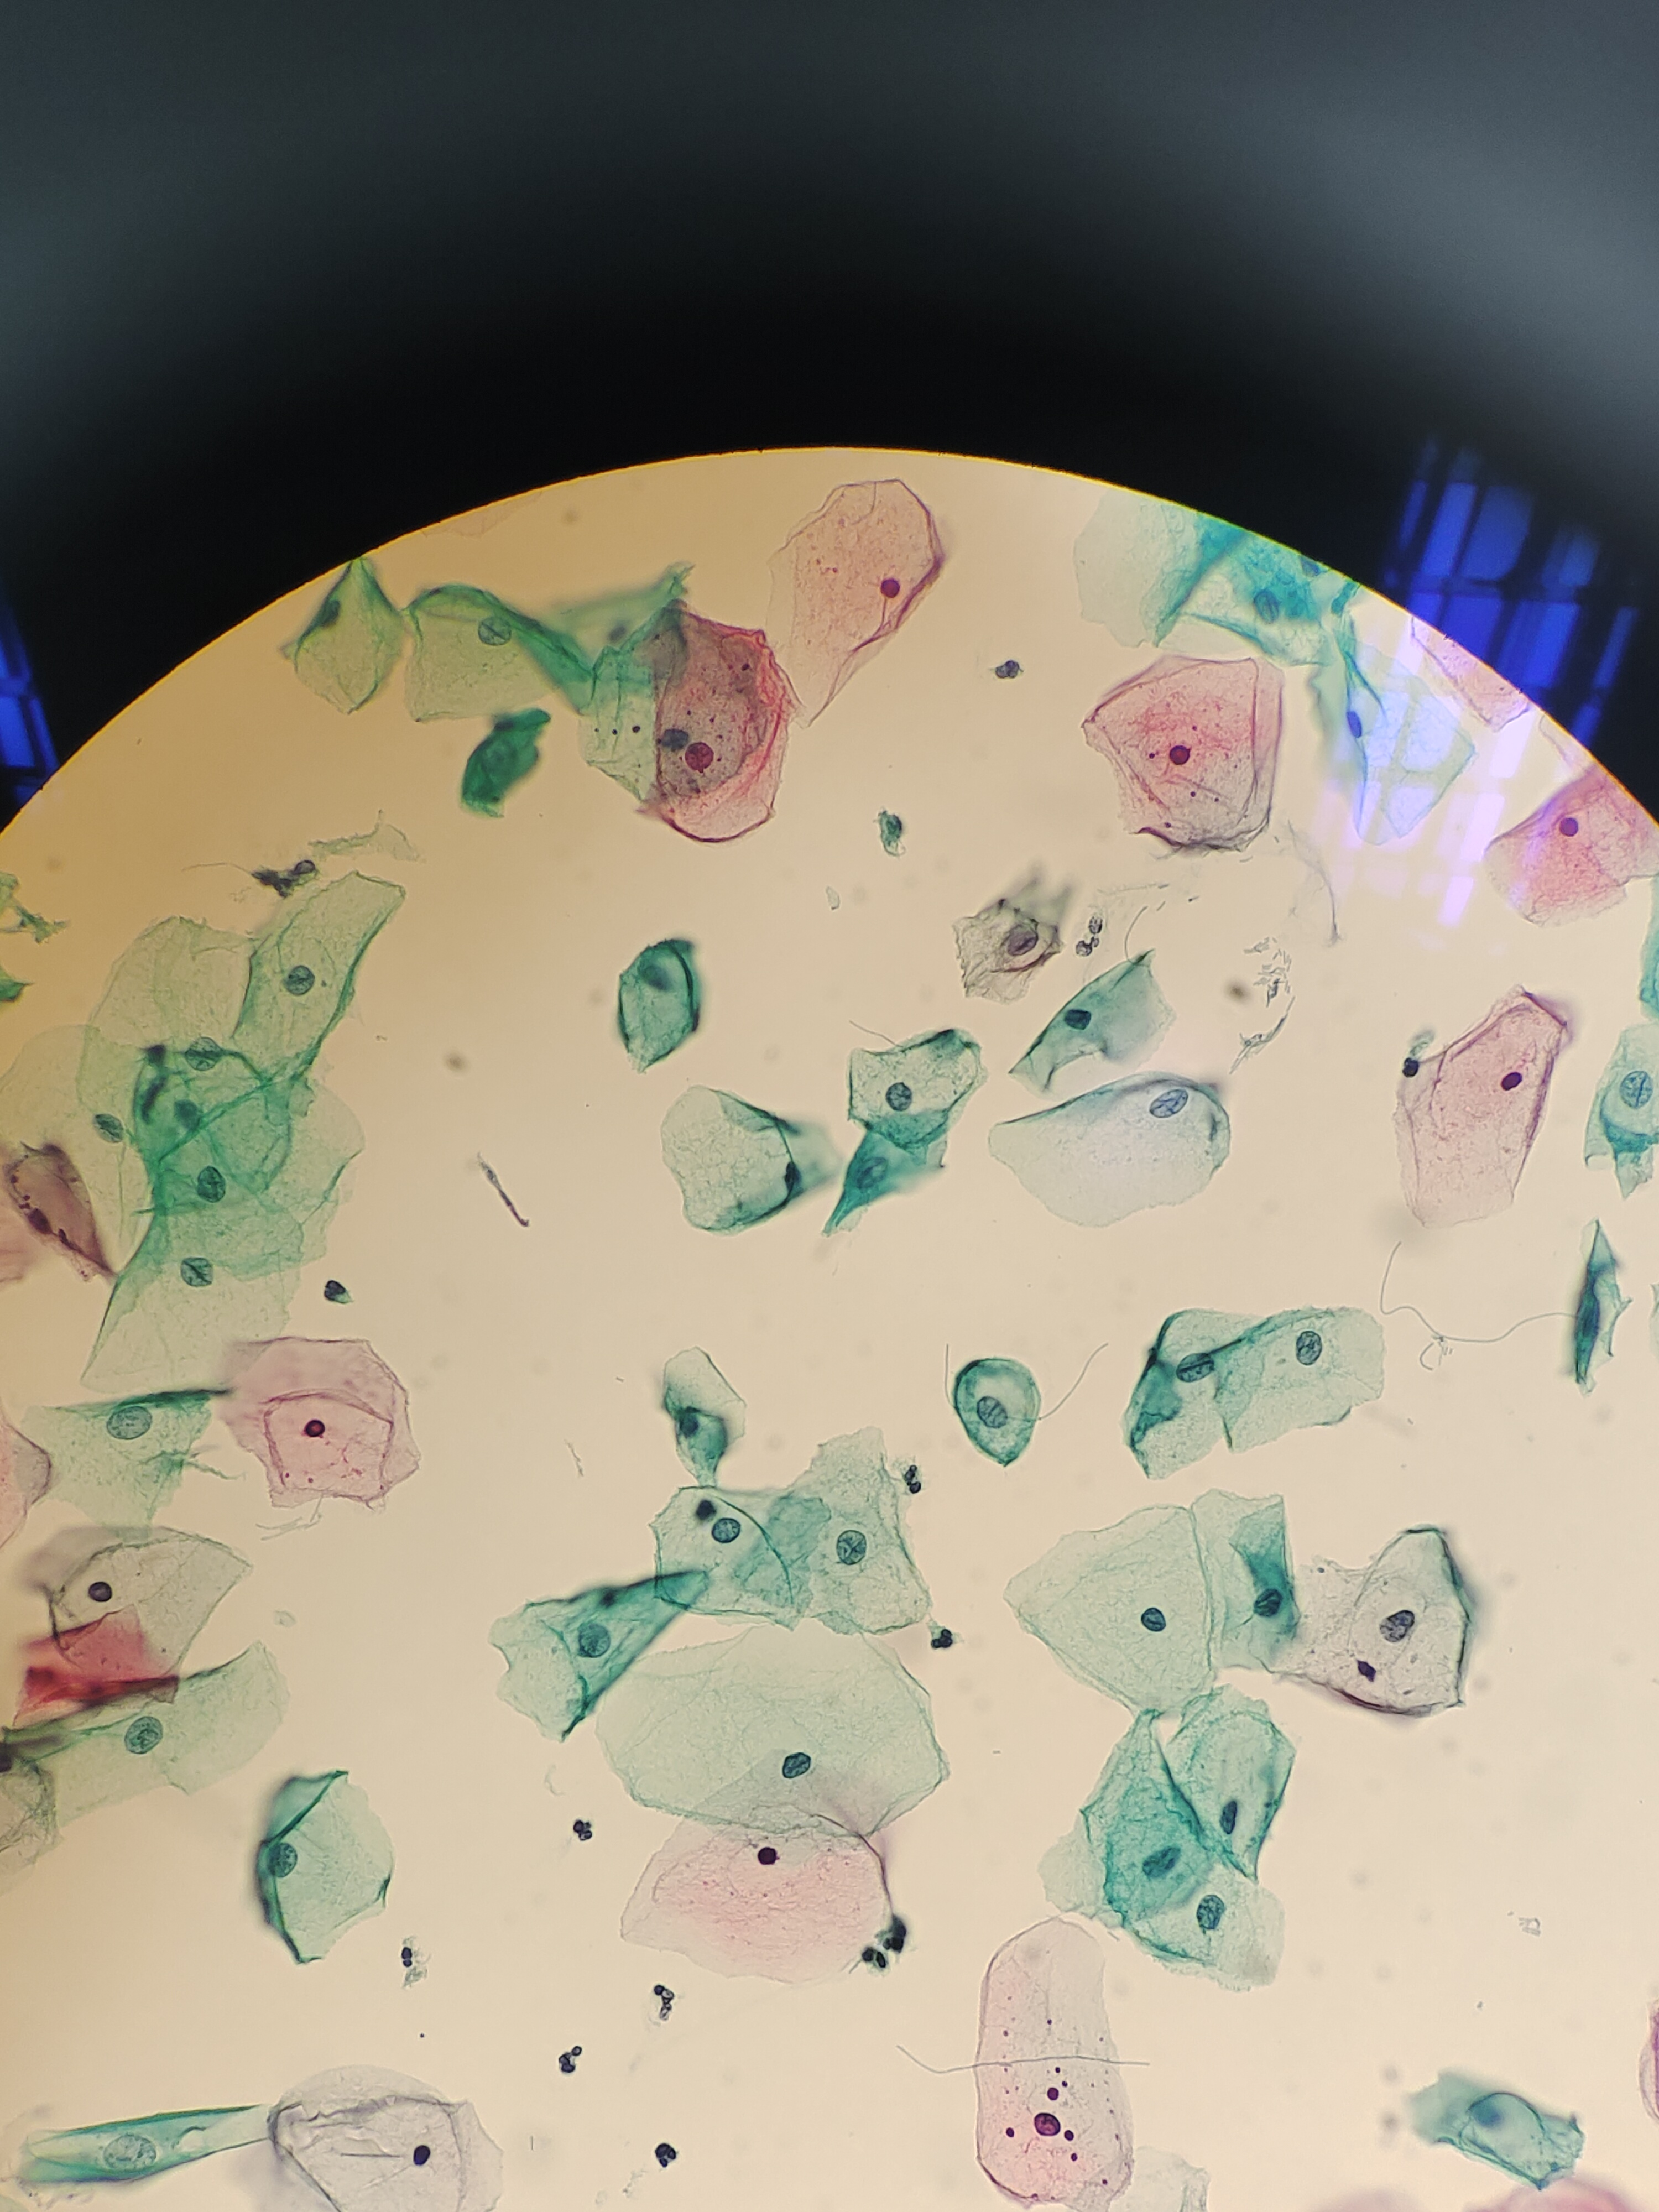

TCT

性别

女

年龄

35岁

一般病史

分泌物多,外阴痒半个月,宫颈光,HPV阴性。老师们,有些核偏大细胞,有事吗?

标本类型

宫颈

制片方法

液基

染色方法

NILM